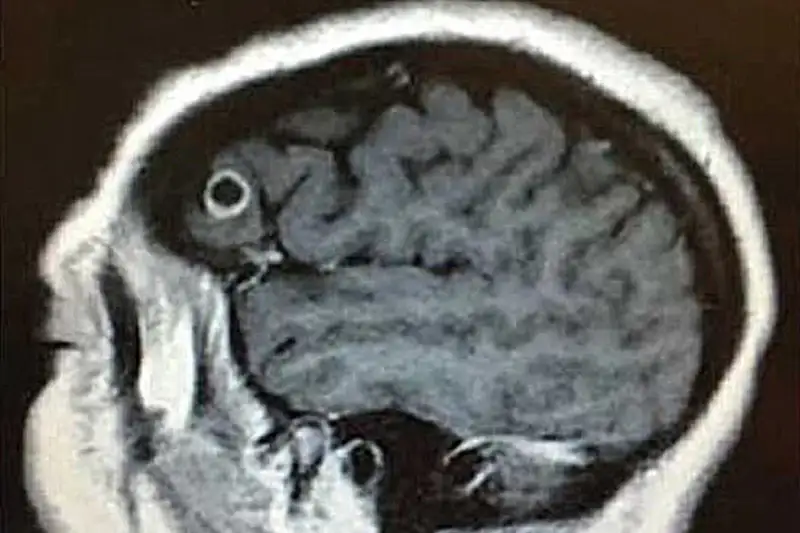

АҚШ-та адам миы құрттап кеткен